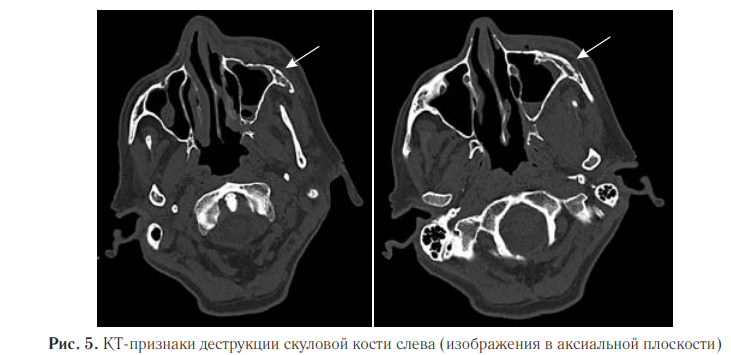

Деструктивные изменения были обнаружены и в левой скуловой кости (рис. 5).